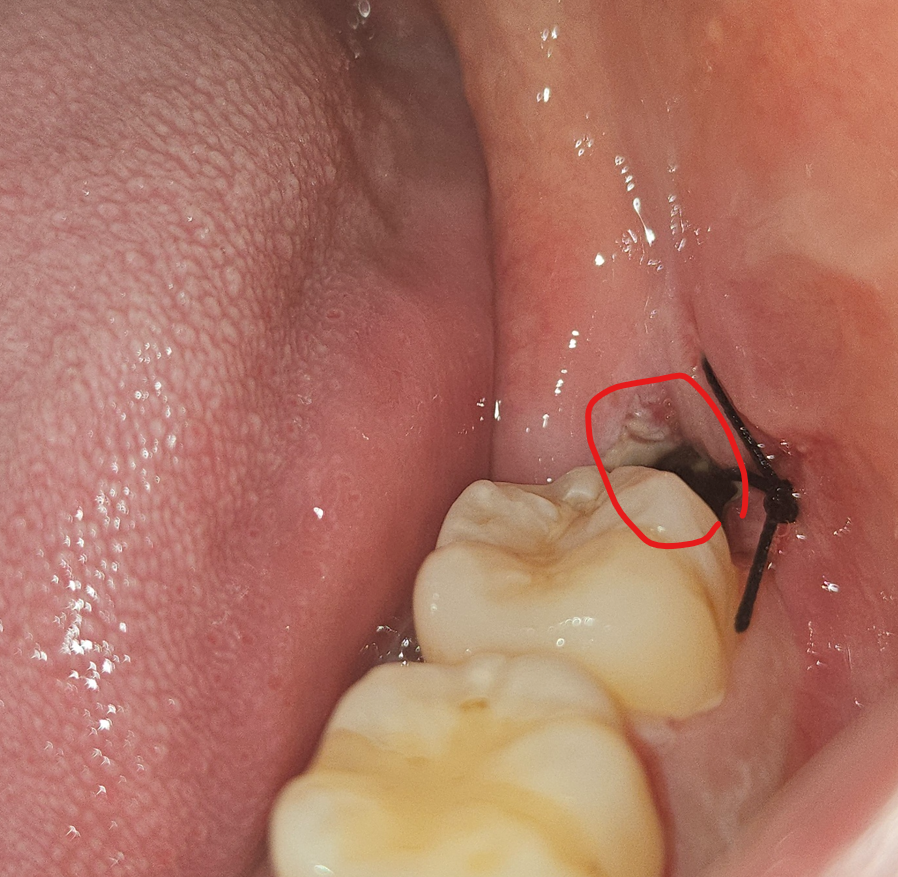

사랑니 발치 후 상태에 대해 질문 드립니다.

제가 3일 16시쯤 매복사랑니 발치를 하고 현재는 80시간정도 지났습니다.

1. 사진 에서 빨간색으로 표시된 부분은 왜 이렇게 까만건가요? 혹시 감염이 된건지 궁금합니다.

3. 사진에서 특별히 이상 소견이 있는지 궁금합니다.

• 1번 째 사진

치아를 발치 한 후 공간이 검게 보이거나 혈병입니다. 일주일 정도면 거의 통증이 없어집니다.

1.검게 보이는 것은 발치한 자리 구멍으로 보이며 원래 검게 보입니다.

표시한곳은 치아를 뺀공간이라 까맣게 보이는 거 같습니다. 진통제는3일정도 드셔야될것같습니다.사진상으로 큰 문제가 잇어 보이진 않습니다.